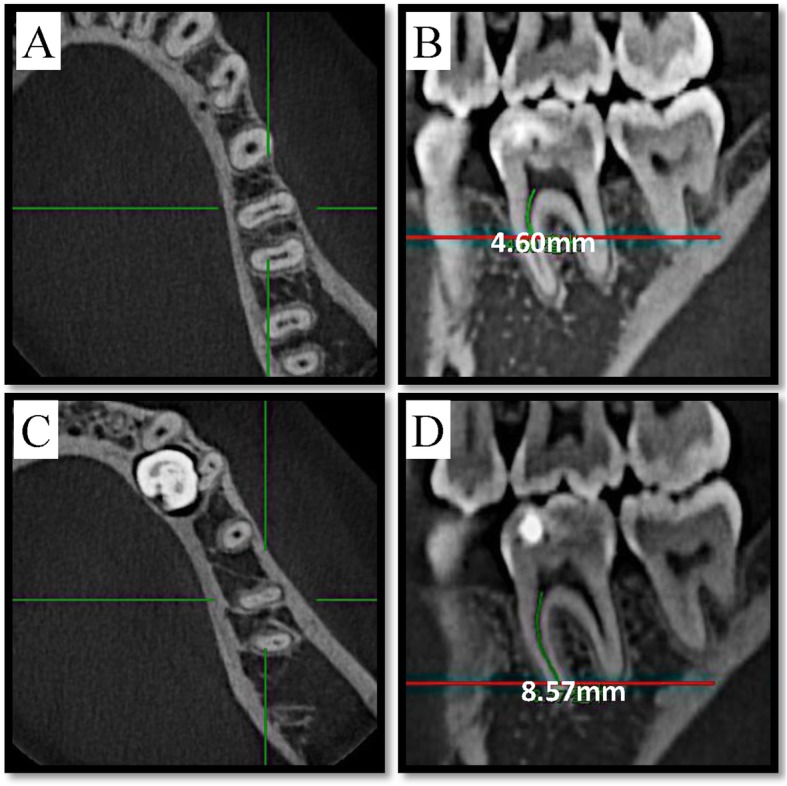

A NewTom VGI (QR Srl, Verona, Italy) CBCT unit with an isotropic voxel size of 0.125 mm, 110 kV and 2.79 mA as exposure parameters, 8 cm × 8 cm as field of view and 3.6 s as exposure time was used for this study. In a dimly lit room, the Carestream Dental Imaging Software 3D module v2.4 (Carestream Health, Inc., Rochester, NY) was used to inspect CBCT images on a Dell Professional P2213 workstation (Dell, Round Rock, TX) using a 22-in. monitor at a resolution of 1680 × 1050. Two endodontists with five years of clinical experience, who were helped by a radiologist experienced in endodontics, evaluated all CBCT images independently and discussed for any disagreement until consensus was reached. Image evaluation was conducted in five sessions with a time interval of one week between each session. Data regarding demographics, side of mandible, presence of separated distal-lingual roots, presence of isthmuses and MM canals, and the length of isthmuses (the distance between the lower edge and the root canal orifice minus the distance between the upper edge and the root canal orifice, as shown in Fig. 1) in the mesial root were recorded (Additional file 1: Raw data).

Fig. 1.

Measurement of isthmus length using Carestream Software’s built-in measuring tool. The red line in figure (b) corresponds to the level of figure (a), the red line in figure (d) corresponds to the level of figure (c). (a) The first cross-sectional picture exhibiting the isthmus in coronal-apical direction, which corresponds to the upper edge of isthmus. b linear distance of the upper edge of isthmus to the root canal orifice is 4.60 mm. c The first cross-sectional picture where the isthmus disappears in coronal-apical direction, which corresponds to the lower edge of isthmus. d linear distance of the lower edge of the isthmus to the root canal orifice is 8.57 mm. Thus length of the isthmus = linear distance of the lower edge of the isthmus to the root canal orifice - linear distance of the upper edge of the isthmus to the root canal orifice, which means 3.97 mm = 8.57 mm - 4.60 mm